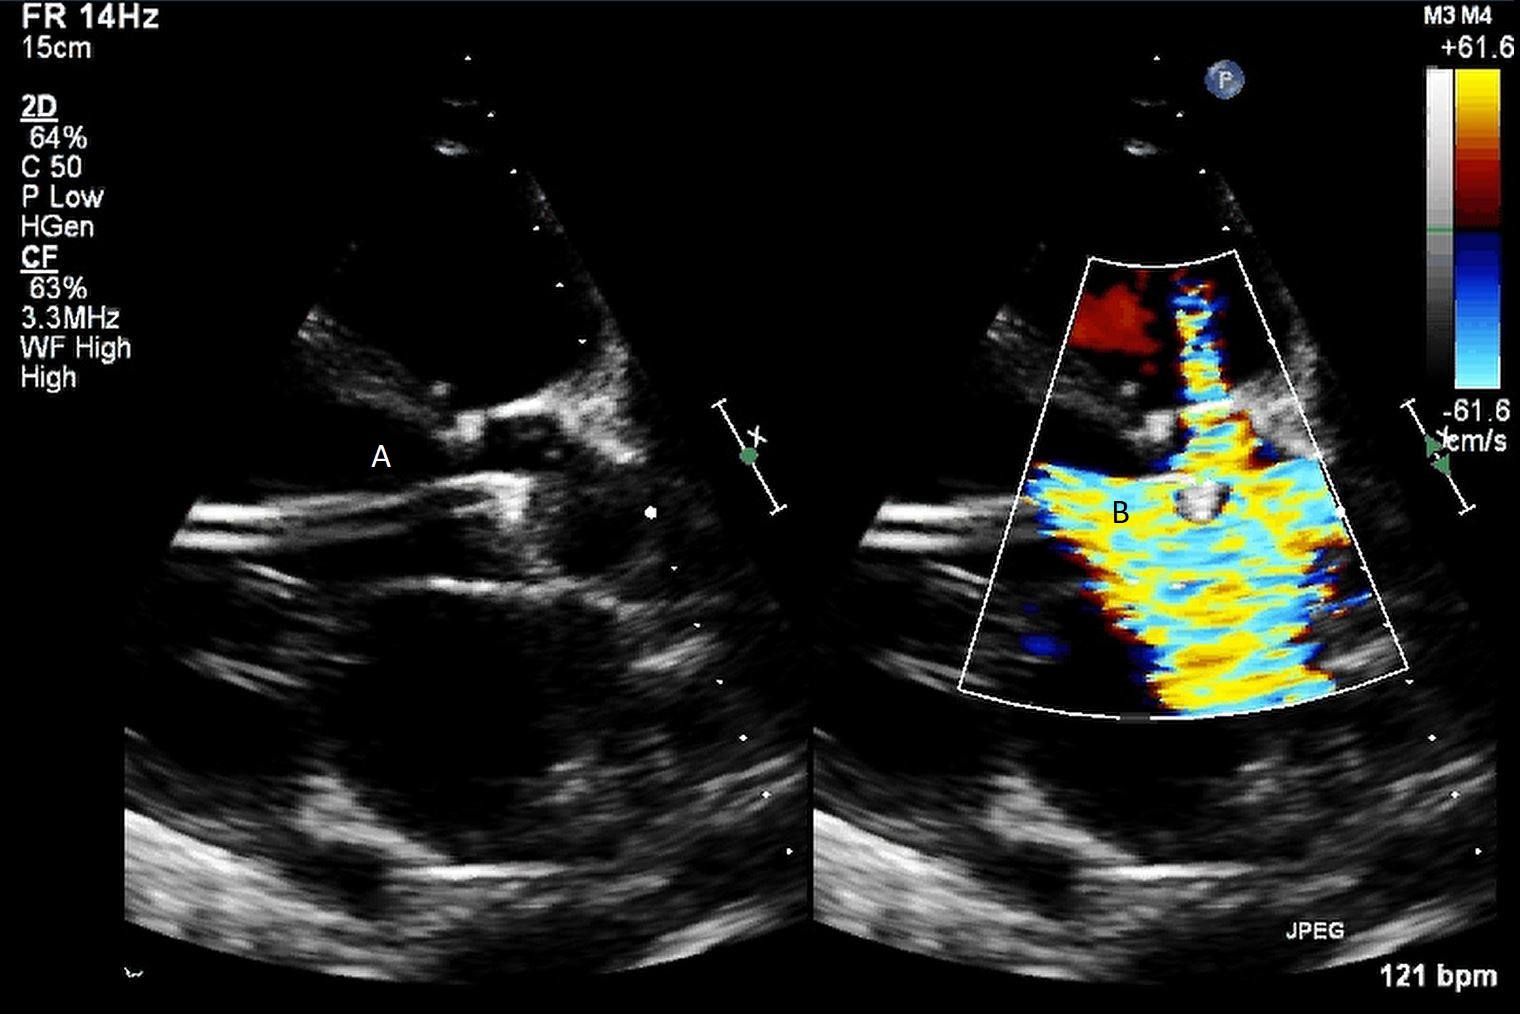

Protek Duo (A) visualized in RV. Its placement caused disruption of tricuspid valve with resultant tricuspid regurgitation seen on color flow imaging (B).

The TandemHeart Protek Duo is a percutaneous right ventricular assist device (RVAD) placed via a dual-lumen 29 French sheath in the right internal jugular vein. The inflow lumen is situated in the right atrium and outflow lumen in the main pulmonary artery. The port lumens are connected externally to a TandemHeart centrifugal pump [31]. As this is generally placed in the operating room, intra-operative TEE can be used to help guide placement. Similar to the Impella RP, bicaval and midesophageal 4 chamber views can visualize the inflow cannula and RV inflow-outflow view and upper esophageal views can be used to visualize the outflow cannula (Figs. 13,14,15). On occasion, its placement can result in distortion of the tricuspid valve morphology with resultant tricuspid regurgitation (Fig. 16). If this is noted, cannula repositioning can be considered. TEE can also help in identifying the ideal pump speed for a patient on TPD support. When utilizing a “ramp protocol”, where the pump speed is progressively increased intraoperatively, midline interventricular septal position can indicate an appropriate amount of RV support [32].